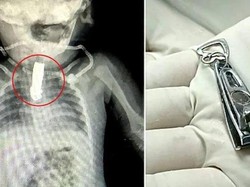

Pria di India, Bhau Lackhe (19) dinyatakan mati otak oleh dokter. Namun, kejadian yang terjadi pada Jumat (5/9/2025) membuat keluarganya terkejut..